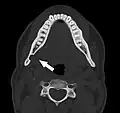

Stafne bone cavity seen on coronal CT -

Stafne bone cavity seen on axial CT